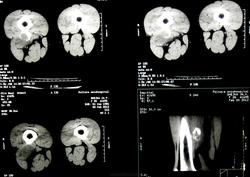

Молодая женщина 25 лет. Жалобы на боли по задней поверхности бедра. Травма была. но этой зимой. По некоторым мнениям - обызествленная гематома.

Материалы представленые. Оригинала КТ нет.

Действительно, по R-грамме производит впечатление обызвествлённой гематомы. Я не занимаюсь КТ, но на представленных сканах это образование по плотности как кость ( оссифицирующий миозит?). Не знаю, возможно ли это в ваших услових, но можно рекомендовать УЗИ области бедра.

По вот этому срезу у меня складывается впечатление, что этот участок связан с костью - экхондрома? параоссальная хондрома? образование мягких тканей (фиброма)? Мне кажетс, что для того, чтобы обызвествилась гематома травма должна быть давненько, поэтому для меня обызвествленная гематома под большим вопросом.

Абсолютно с Вами согласен, уважаемая Фаина. для меня она тоже - под большим вопросом. потому и прошу помощи. честно говоря большого собственного опыта работы с опухолями костей у меня нет. не та специфика учереждения.

1. УЗИ сегодня должны были делать. и пункционную биопсию одновременно. о результатах доложу.

2.Если это обызествленная гематома то. к чему реакция периоста, да еще и ТАКАЯ. да и мягкотканный компонент присутствует вокруг.